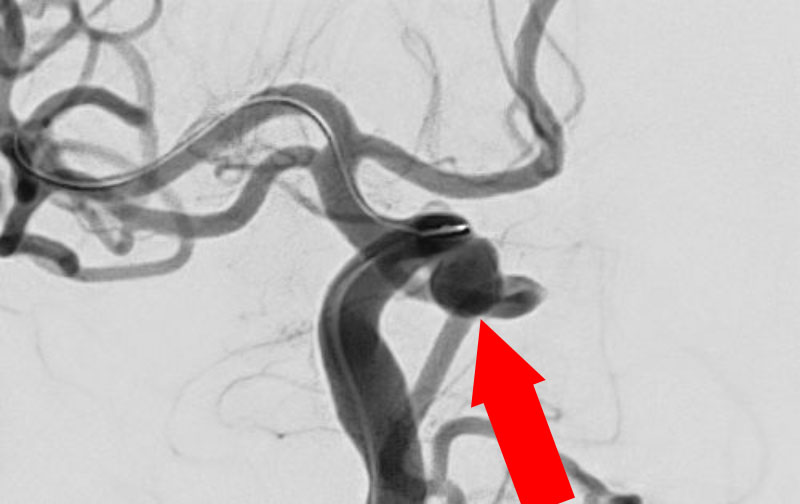

No.1628 手術前